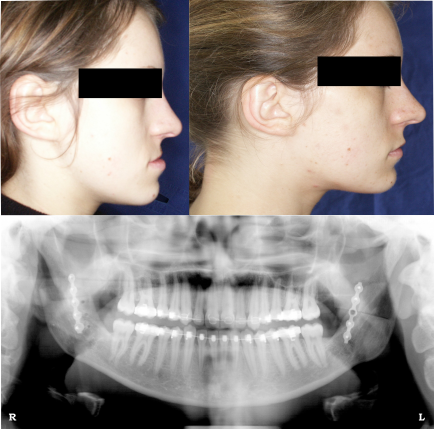

Fehlbisslagen (Dysgnathien) gehen meist mit einer Veränderung des Gesichtsprofils einher. Somit sind nicht nur funktionelle sondern auch ästhetische Beeinträchtigungen vorhanden. Die Korrektur solcher Veränderungen ist eine fachübergreifende Herausforderung. Sowohl Kieferorthopäden als auch Zahnärzte und Mund-Kiefer-Gesichtschirurgen müssen solche Behandlungen gemeinsam abstimmen, planen und durchführen. Nach einer klinischen, instrumentellen und funktionellen Diagnostik wird fachübergreifend das Behandlungskonzept festgelegt. Diese Behandlungen finden in der Regel unter stationären Bedingungen in der Klinik statt. Die Eingriffe selbst werden in Vollnarkose innerhalb der Mundhöhle durchgeführt. In diesem Fall wurde der Unterkiefer um 10 mm rückverlagert und mit s.g. Titanplatten stabilisiert. Nach Knochenheilung wird dieses Material in der Regel belassen, da es keine Beschwerden verursacht, kann aber bei Bedarf auch wieder entfernt werden. Wir begleiten diese Behandlungen in unserer Praxis im Rahmen der Vor- und Nachbehandlung. |